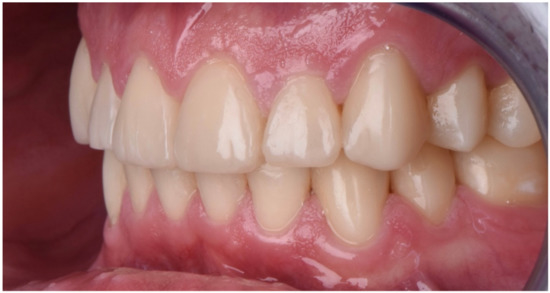

2. Clinical Report

2.2. Restorative Phase